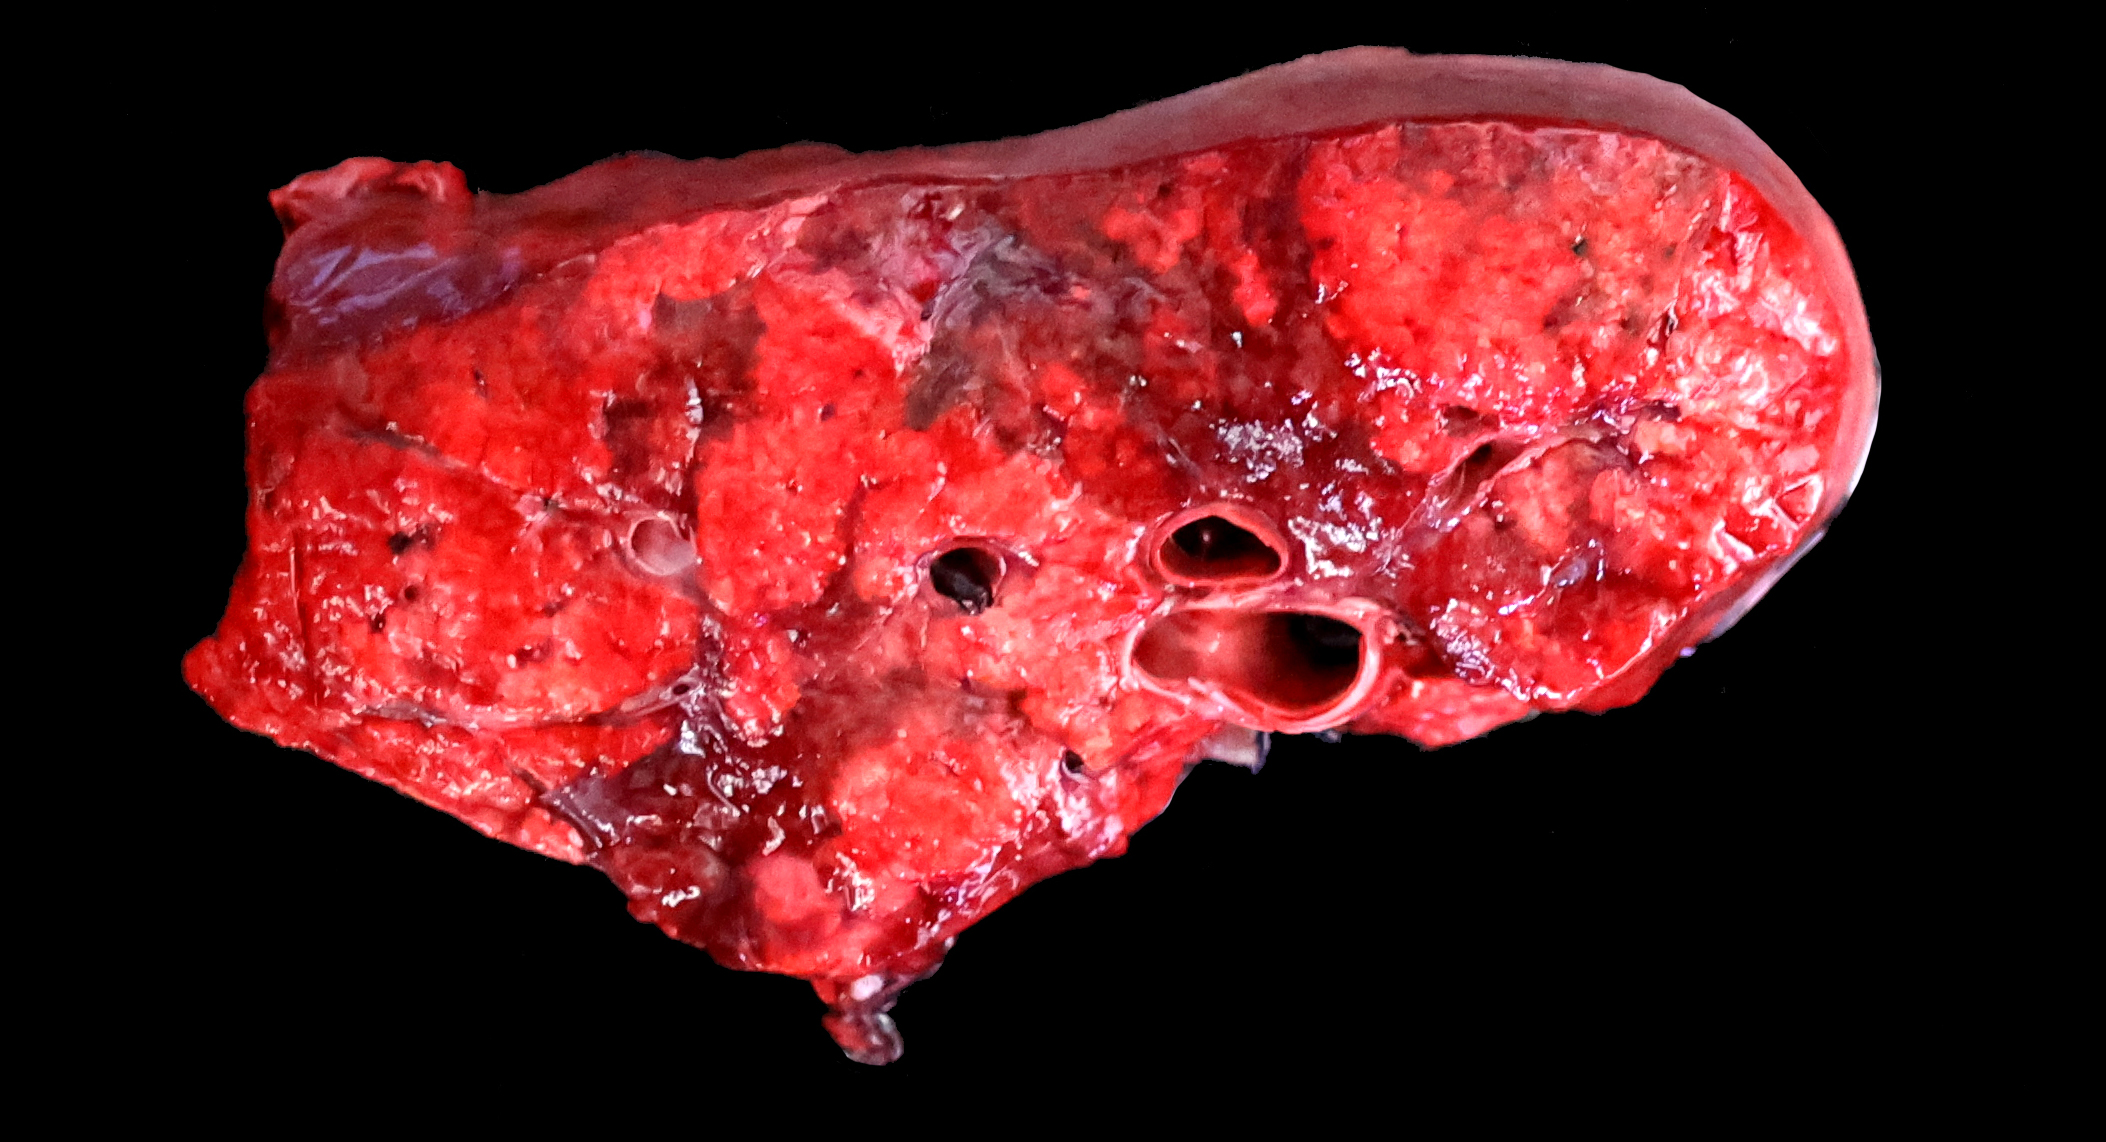

Gross Pathology:

The lungs are diffusely swollen with a lobular pattern. On the cut surface, red areas of pulmonary consolidation are seen in a lobular pattern, separated by unaffected lung lobules. Moderate amounts of thick tan exudate are noted in the airways. The trachea contains moderate amounts of stable foam. The tracheobronchial lymph nodes are enlarged.

Typical pathological changes in equids with viral pneumonia include pulmonary consolidation in a lobular pattern separated by unaffected or overinflated lung lobules, or less commonly, a diffuse pattern of pneumonia.1 EIV infections complicated by secondary bacterial infections are characterized by fibrinosuppurative exudate and pulmonary consolidation, mostly restricted to the cranioventral pulmonary lobes (bronchopneumonia).1,12,13 Histopathologically, acute stages typically reveal rhinitis and tracheitis with epithelial necrosis and infiltrates of lymphocytes in the lamina propria. Subacute to chronic lesions consist of epithelial hyperplasia and squamous metaplasia.6,11 Affected lungs exhibit bronchointerstitial pneumonia with hyaline membranes in the alveoli, type II pneumocyte hyperplasia, and necrotizing bronchitis/bronchiolitis. Secondary bacterial bronchopneumonia may also develop.4,6,12

Grossly, an influenza-infected lung has a ?checkerboard? appearance with random, alternating areas of dark red atelectasis and light pink, aerated lung. This pattern manifests because influenza does not uniformly infect every cell it comes into contact with due to varied densities of sialic acid receptors on the host cells. Dark red to purple areas of consolidation represent collapsed alveoli whose airway has been clogged by exudate and which can no longer pass air through to the alveoli.. These solidified, dark red sections contrast sharply with the lighter-colored, air-filled alveoli.